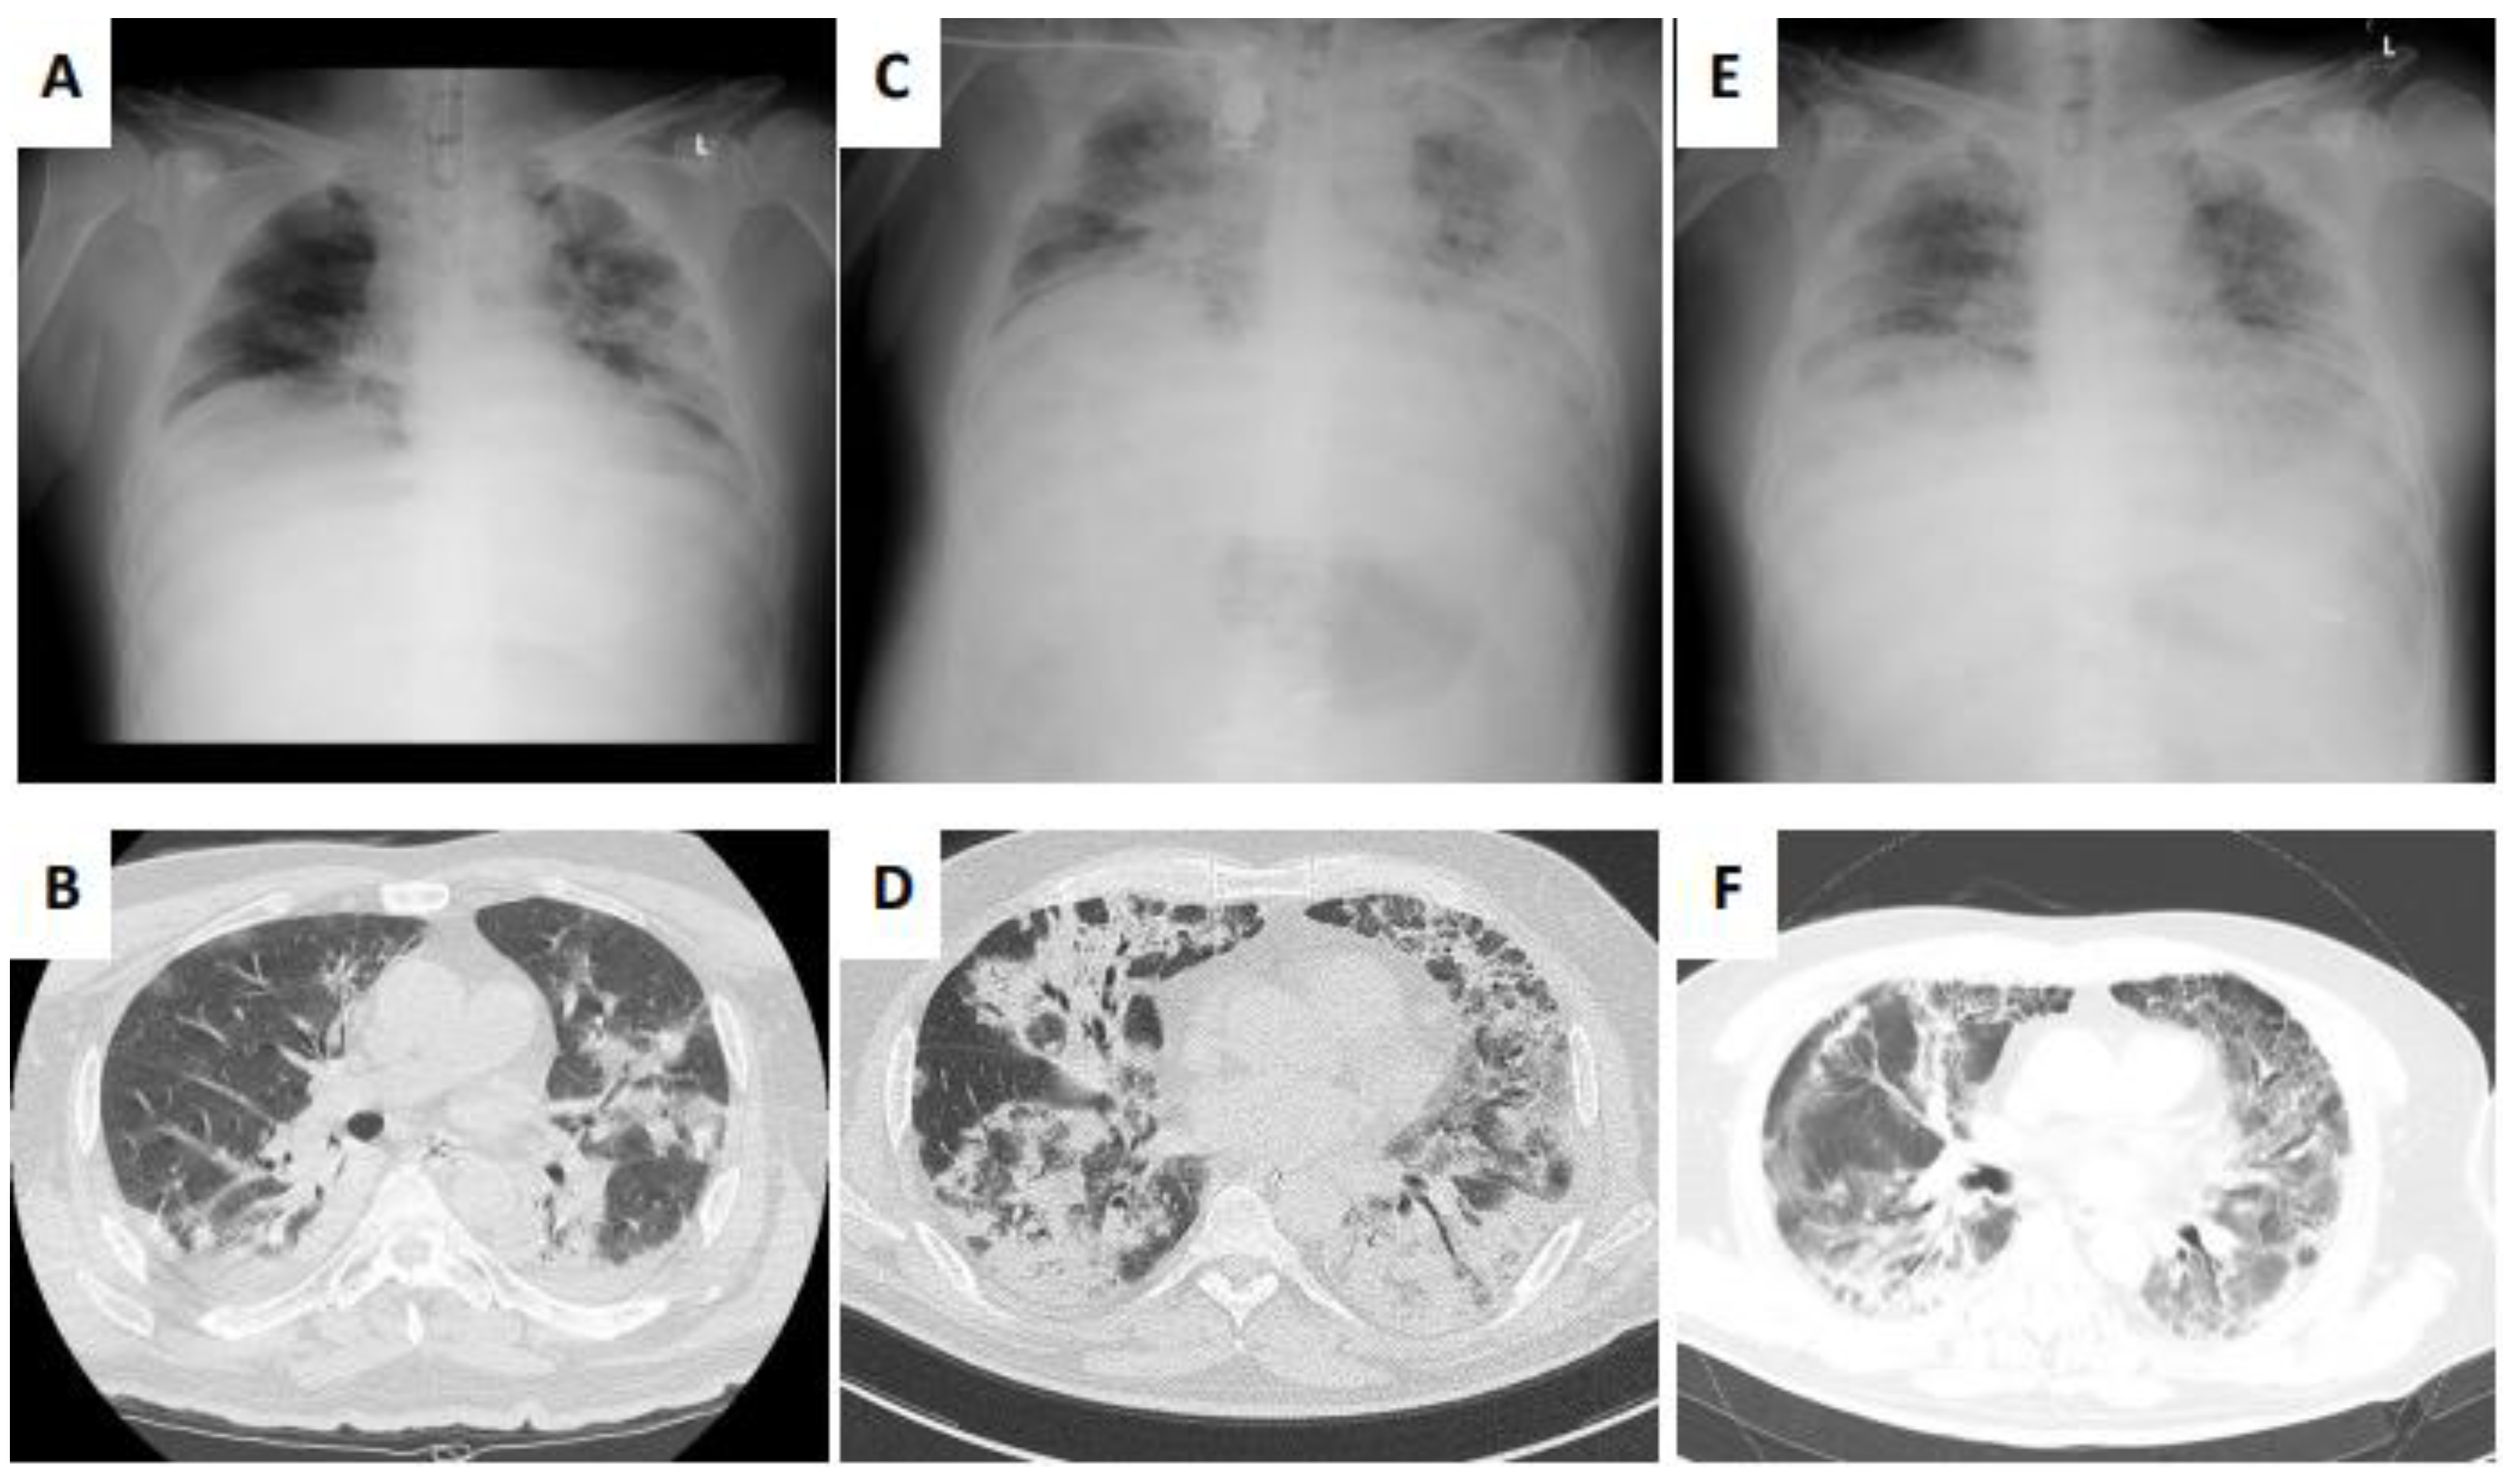

2. Case Presentation